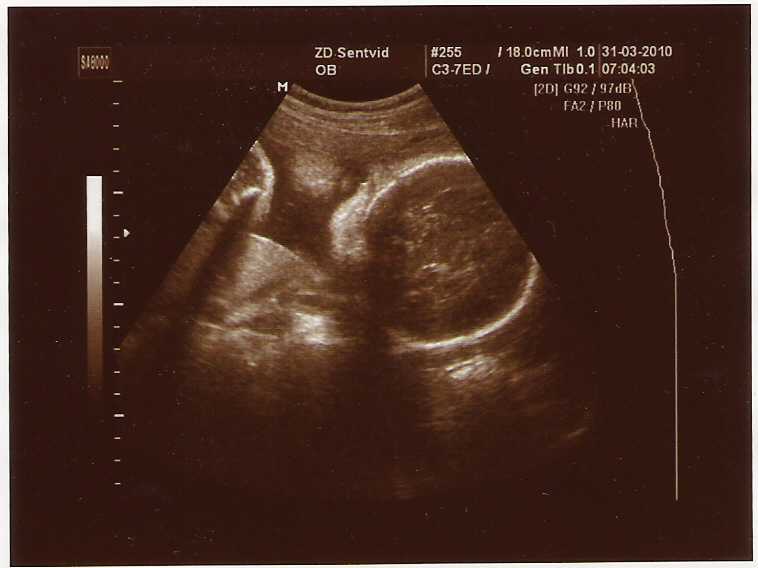

ultrazvokSKRIVNOSTNI POROD, OBIČAJI OB ROJSTVU PRED PETDESETIMI LETI IN DANES

V raziskovalni nalogi raziskujeva pripravo na porod, kje so ženske rojevale, kakšni so možni zapleti pri porodu ter kakšni običaji so spremljali nosečnost in porod nekoč (pred približno petdesetimi leti) in danes. Ugotovitve raziskovalne naloge temeljijo na dvajsetih izčrpnih intervjujih z mamami, ki so rodile otroke pred petdesetimi leti, z mladimi mamicami danes, z upokojeno babico Milko Jeraj ter z babico, s porodničarjem in z medicinsko sestro, ki delajo v porodnišnici danes. Analizirali sva strokovni reviji Babiški vestnik in revijo Utrip ter porodne knjige babice Milke Jeraj. Rojstvo otroka je za vsako žensko začetek novega obdobja, ki ga mora sprejeti, da lažje prestane porod in z njim povezane bolečine. Ugotovili sva, da ženske včasih psihično niso bile pripravljene na porod in jih je bilo zato poroda strah. Danes so ženske precej bolje pripravljene, predvsem po zaslugi šol za starše, številnih revij, knjig in spletnih forumov. Nekoč ženskam moški niso veliko pomagali pri gospodinjskih opravilih, danes pa enakovredno opravljajo gospodinjska dela, kar je predvsem v času po porodu mladim mamicam v veliko pomoč. Porod in rojstvo spremljajo določene navade in ljudske modrosti, npr. ta, da šest tednov pod posteljo porodnic leži smrt, zaradi tega morajo še posebej paziti na svoje zdravje. Sam porod nekoč in danes se bistveno ne razlikuje, razlika je le v tem, da imajo ženske danes na razpolago veliko izbiro protibolečinskih terapij, včasih pa tega ni bilo. Zapleti se lahko pojavijo enaki kot nekoč, vendar danes vse ženske rodijo v porodnišnici in je ob takih primerih zdravniška pomoč pri roki. Ob rojstvu otroka nekoč večinoma ni bilo v navadi čestitanje, moški so le otroka »zapili«. Danes je čestitk in daril veliko več. Nekoč je bilo v navadi, da so ženskam po rojstvu otroka prinesli kokoš in jajca, ker je bila za žensko po porodu kurja juha najbolj priporočljiva. Danes se ta navada izgublja, med darili pa danes prevladujejo oblačila in igrače za otroka. Po najinem vzorcu otrok sva ugotovili, da sta bili pred petdesetimi leti najpogostejši imeni otrok Marija in Marjan, danes pa Lana in Luka.